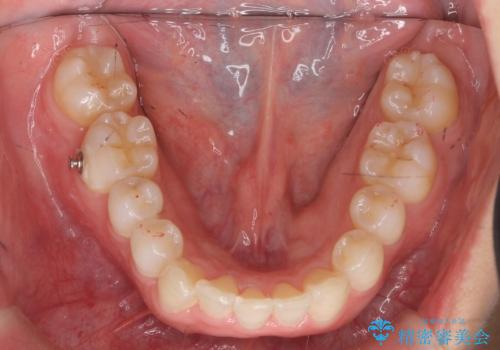

前歯をさげたい 歯を抜かずに マウスピース矯正で治したい

- 上の前歯が出ているとのことで来院。

歯を抜かずに、上の奥歯を後ろにさげつつ上の前歯を小さく少し削る処置を行い前歯の角度を修正しました。

右上下の奥歯もすれ違い咬合も、治療で改善しています。

下の前歯が生まれつき3本でしたので上下の正中は合わない仕上がりとなります。